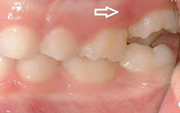

Esimese jäävmolaari ektoopiline lõikumine

Ravijärgne seis. Jäävhammas on täielikult lõikunud.

) Röntgenülesvõte. Ülemise esimese jäävmolaari lõikumine on takistatud 2. piimamolaari tõttu